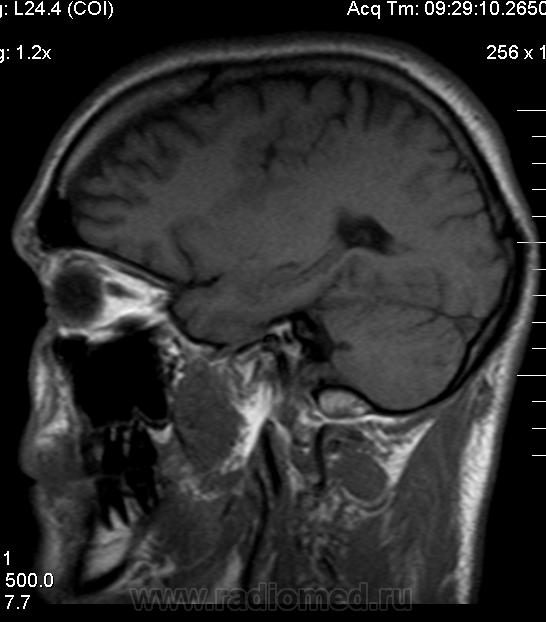

Мужчина 32 лет. Из анамнеза: перинатальное повреждение ЦНС, ДЦП, дизартрия, правосторонний верхний монопарез. С 16 лет приступы эпилепсии.

Аплазия прозрачной перегородки. Шизэнцефалия с открытыми краями в лобно-теменной области слева. Шизэнцефалия с закрытыми краями в лобной области справа? Утолщение коры по контуру расщелин и в области глазничной извилины правой лобной доли. Микрогирия? Гиперостоз костей свода черепа. Уважаемые коллеги, возможно я ошибаюсь, или есть еще аномалия?

сочетания отсутствия прозрачной перегородки и дисплазии ( разно степени выраженности) зрительных неровов  указывает на септоптическую дисплазию-нарушение развития в области средней линии , сопровождается мнггими другими структурными аномалиями, чаще шизэнцефалией.

Спасибо. Как тогда лучше сформулировать заключение? МР-картина кортикальной дисплазии : двусторнняя шизэнцефалия с утолщением коры по контуру расщелин, микрогирия в лобной области справа, очаг гетеротопии серого вещества в области  глазничной извилины правой лобной доли. Признаки септооптической дисплазии (гипоплазия зрительных нервов, аплазия прозрачной перегородки). Лиссэнцефалии не вижу. Есть сомнения по поводу шизэнцефалии справа (может быть я запуталась в микрогирии и мерещится шизэнцефалия?) Нет ли какой либо анамалии развития черепа?

На мой взгляд, полимикрогирия двусторонняя (конвекситальные отделы дорзальных отделов лобных долей и частично теменных, а также в базальном отделе полюса правой лобной доли) + закрытая шизенцефалия левой лобно-теменной области. Аплазия прозрачной перегородки (как признаки лобарной голопрозенцефалии).